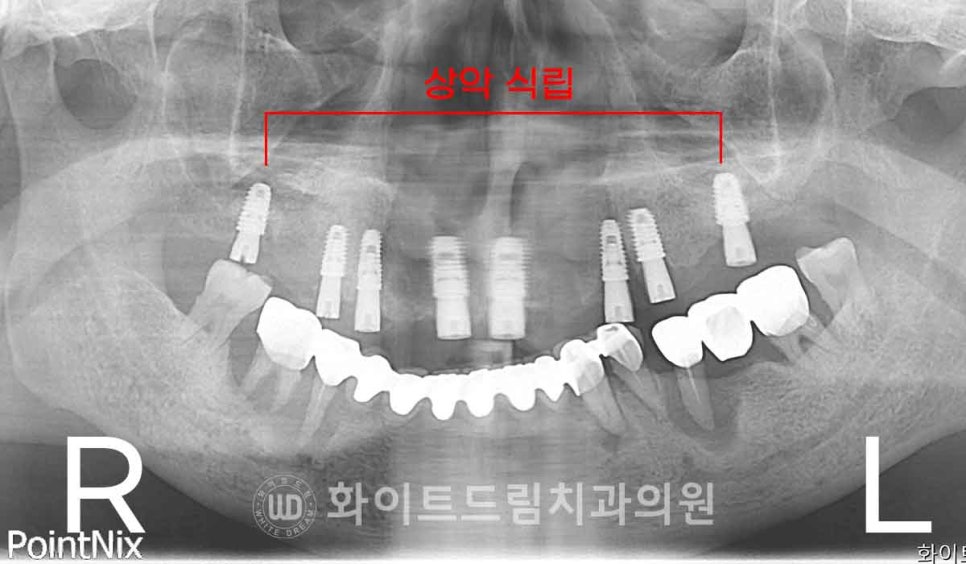

하악에 비해 잇몸뼈의 밀도가 낮고 회복 기간이 조금 더 오래 걸리는

상악부터 수술에 들어가게 되었습니다.

상악 → 하악 순으로 총 2번에 걸쳐 전체 임플란트를 식립하였습니다.

상악 발치 & 임플란트 수술, 서울전체임플란트잘하는치과 : 24.02.15

하악 발치 & 임플란트 수술, 서울전체임플란트잘하는치과 : 24.02.22

염증으로 인해 골 소실이 심했던 부위는 피하고,

상대적으로 잇몸뼈가 남아 있는 부위로 임플란트를 식립하였습니다.

이렇게 하면 임플란트의 초기 고정력을 안정적으로 확보할 수 있을 뿐만 아니라,

불필요한 뼈이식을 줄여 환자분의 부담을 덜 수 있는 장점도 있습니다.

또한 수술 부위의 회복이 원활해져 전체 치료 기간을 단축할 수 있다는

장점도 가지고 있죠. ^^